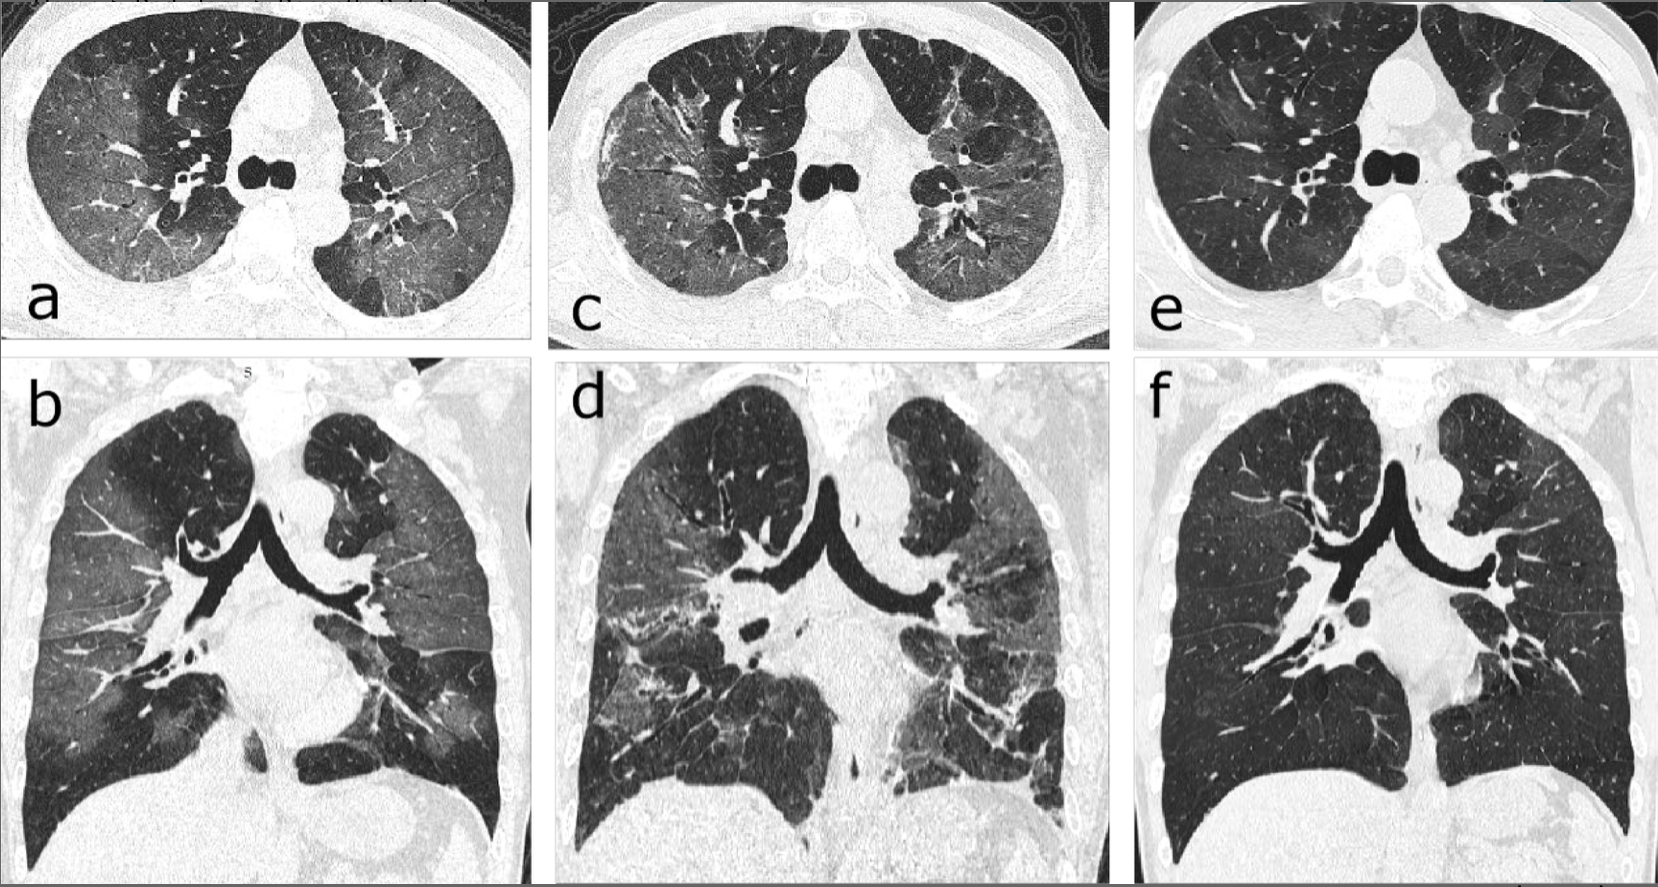

9/25 ct scan covid- In the early stage of the disease (Stage1), CT scans showed in 34 % lesions that involved a single lung lobe and in 212 % no lung involvement (Table 2) The most frequent CT findings of COVID19 pneumonia were GGO, crazypaving pattern, consolidation and linear opacities (Figs 1, 2) The predominant patterns of abnormality changed over timeGlobally, the accepted cutoff for Ct value for Covid19 ranges between 35 and 40, depending on instructions from the respective manufacturers of testing equipment The ICMR has arrived at the Ct value of 35 based on laboratory experiences and inputs taken from several virology labs

A 76yearold male patient with diabetes deceased due to COVID19 Chest CT scan ((a) coronal view, (b) axial viewlung window, and (c) axial viewmediastinal window) showed predominancy of groundglass opacity (GGO) with the bilateral and diffuse distribution Pulmonary involvement (PI) and PI density scores were 16 and 32, respectively According to some doctors, a Ct value of or below indicates high viral load in the patient's body, in addition, Ct values enable doctors to